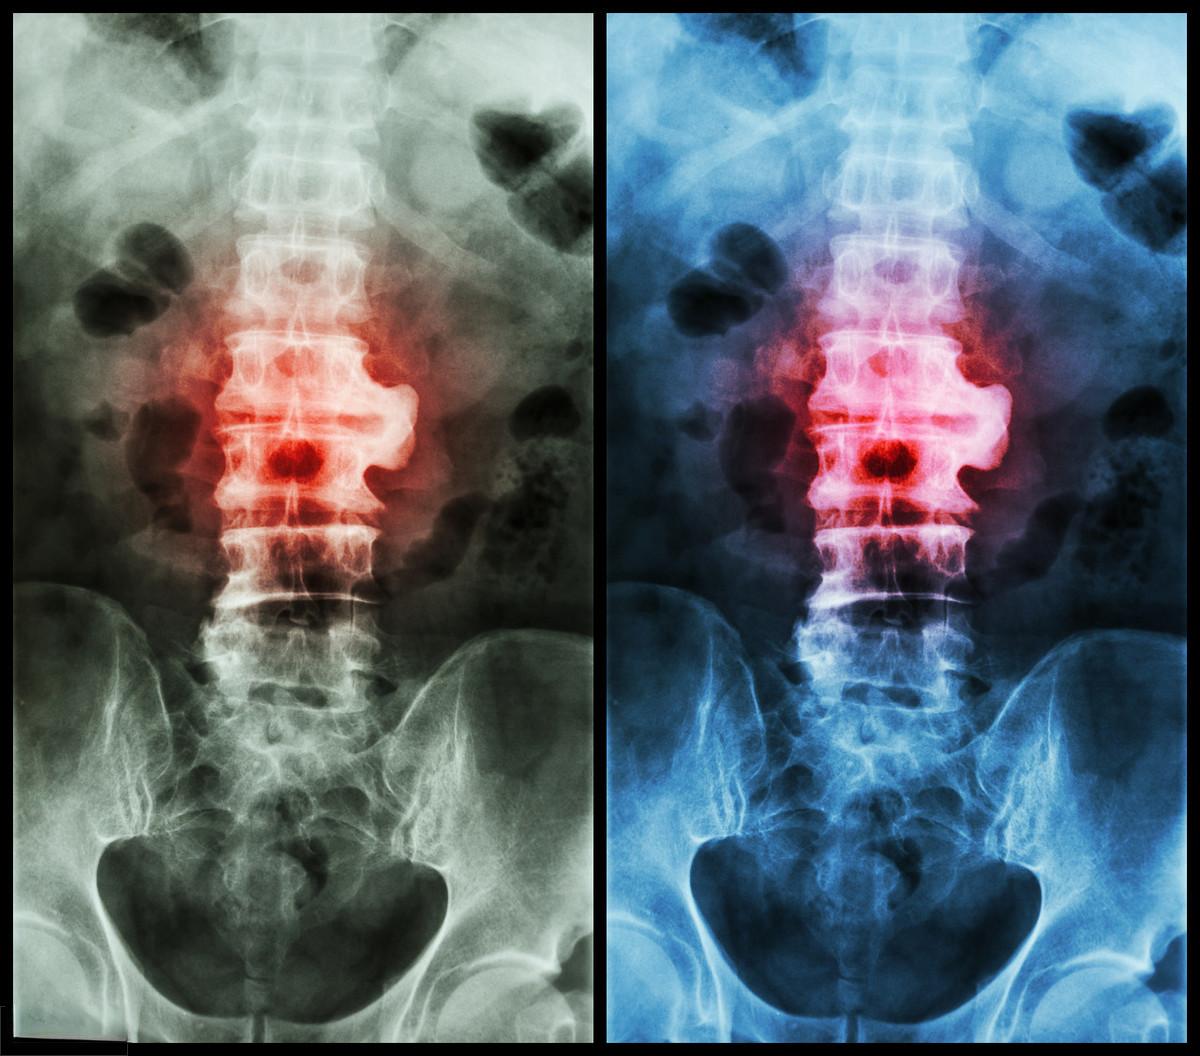

强直性脊柱炎是一种慢性炎症性疾病,影响着全球约1%的人口。 在中国, 约有400万人正在与这种疾病作斗争。 除了广为人知的患者周杰伦,还有无数普通人深受其害。

这种疾病对患者的生活质量造成了严重影响。 研究显示,强直性脊柱炎患者的生理健康得分明显低于心理健康得分,且远低于一般人群。患者常常面临持续的疼痛、关节僵硬和活动受限,严重影响日常生活和工作能力。更令人担忧的是,这种疾病还可能导致患者出现驼背等体型改变,进一步影响其心理健康。